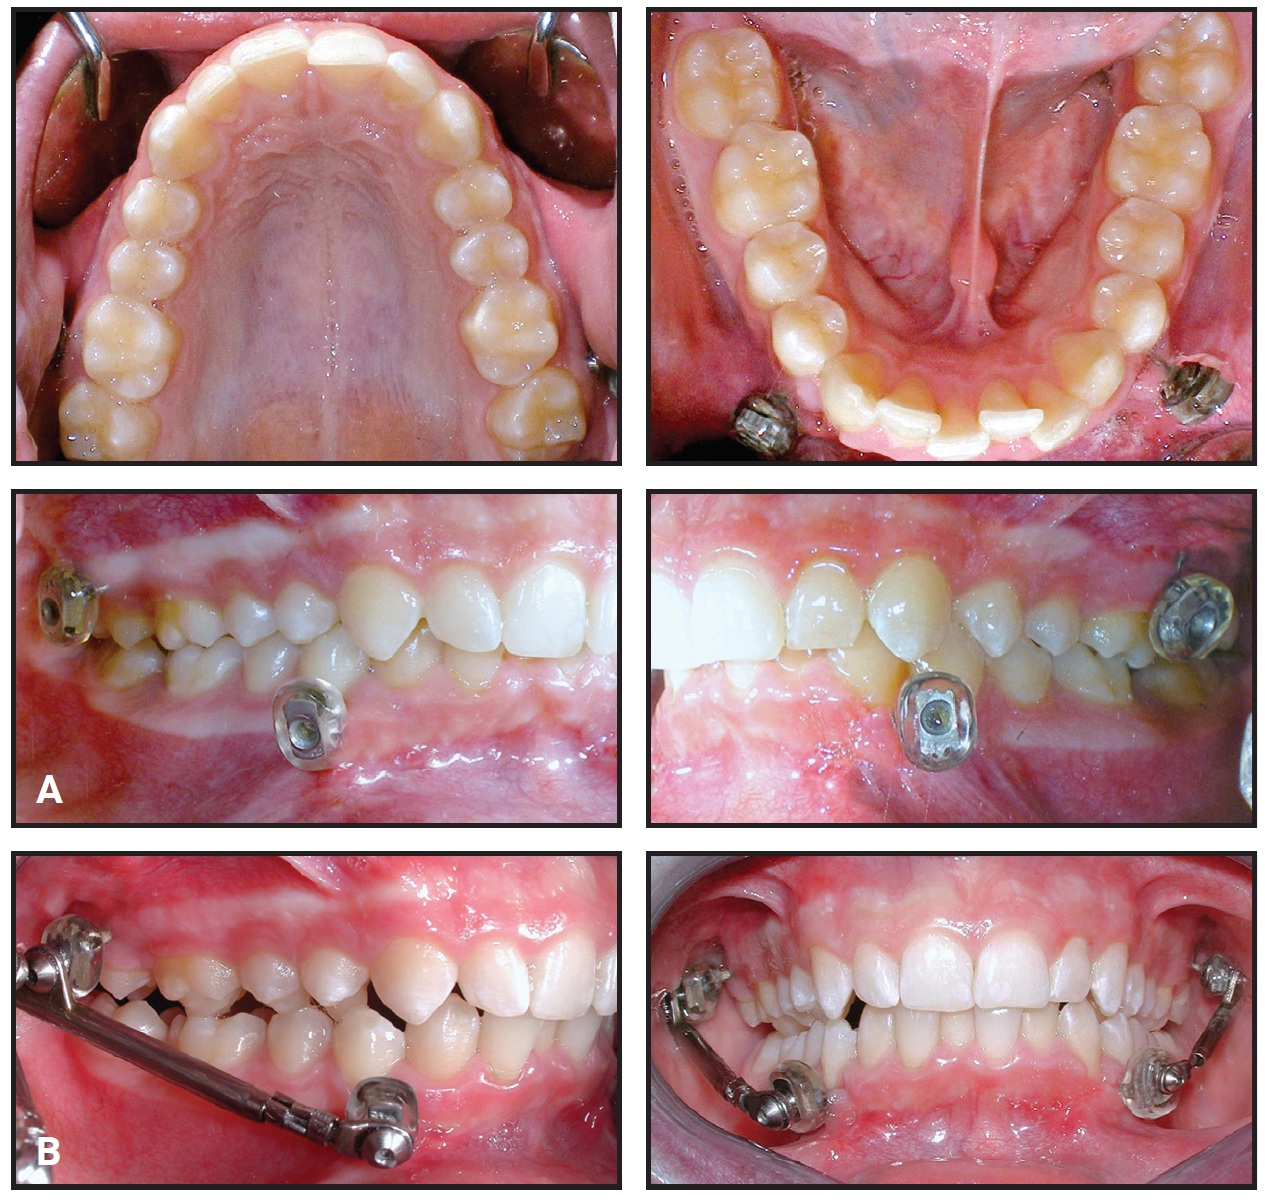

The appliance did not cause any ulceration during treatment. The left MiniScope was removed after seven months to help resolve the dental midline discrepancy. The right MiniScope was removed three months later, when the profile had improved and a dental Class I relationship had been achieved (Fig. 4). The lower incisor inclination was unchanged.

Fig. 4 After 10 months of orthopedic treatment (seven months on left side).

Upper and lower multibracket appliance therapy was then initiated, using .022" MBT*** appliances with archwires progressing from .016" nickel titanium to .019" × .025" stainless steel. Nineteen months later, the overbite had been corrected and the Class I relationship had fully settled (Fig. 5). A lower 3-3 .0195" stainless steel twisted lingual wire was bonded for retention, and an upper Hawley retainer was delivered.

Fig. 5 Patient after 29 months of treatment.

Total treatment time was 29 months. Cephalometric analysis indicated a stable skeletal intermaxillary relationship and an improved profile, with adequate control of the lower incisor positions.

Two years later, the facial and occlusal relationships remained stable (Fig. 6).

Fig. 6 A. Patient two years after treatment. B. Superimposition of pretreatment, post-orthopedic, post-treatment, and two-year follow-up cephalometric tracings.